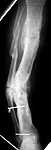

This is a 45 year old gentleman who 8 years ago sustained a midshaft tibia fracture originally treated with plate and screws which became infected. The plate and screws were removed, dead bone was resected and Ilizarov was placed with proximal corticotomy and transport into distal defect. Multiple complications during this including refracture and infection.

He now shows up in my clinic with pain and deformity as seen in the images. He has a draining sinus which drains on and off intermittently. He really wants to save his leg but i think an amputation will serve him best. He has a rigid ankle and midfoot. Currently his ankle is fixed in about 10 degrees of dorsiflexion. He ambulates with crutches because of his pain. He has sensation distally with good capillary refill, no palpable pulse. Angiogram shows all 3 vessels present in leg.